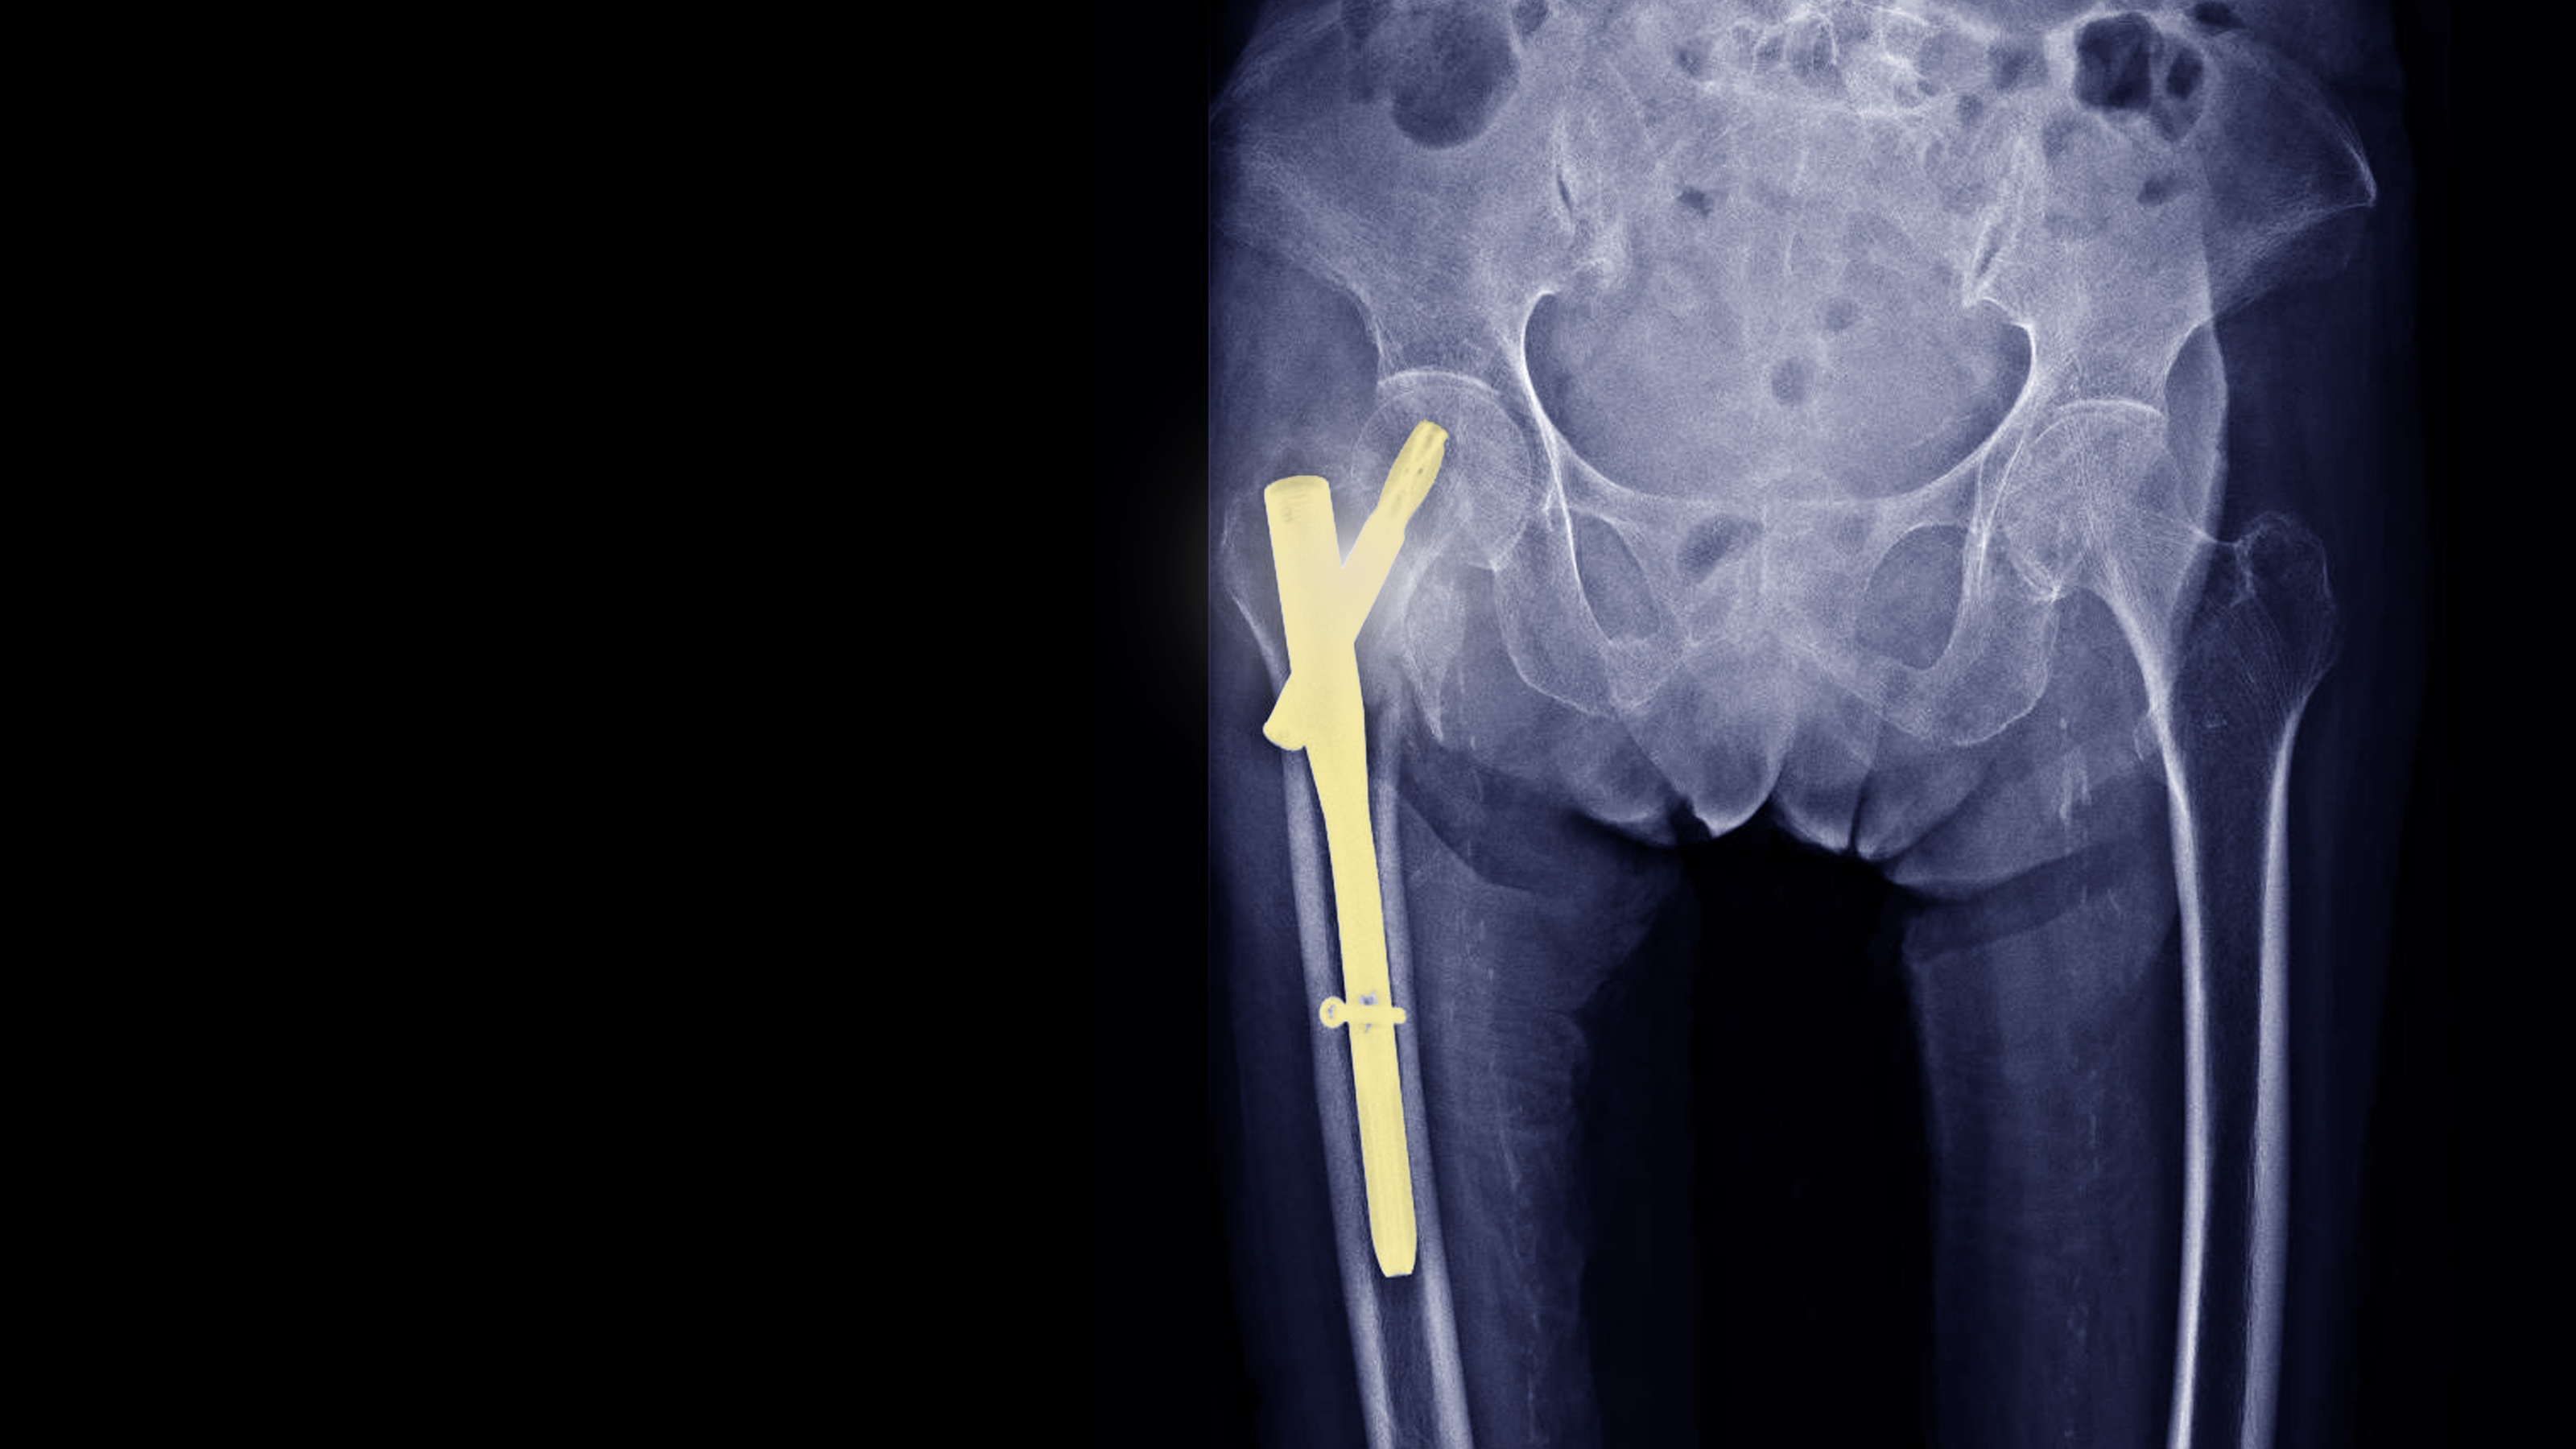

Osseointegration In The Femur, Tibia May Improve Mobility, Quality of Life .

Osseointegration in the femur or tibia may significantly improve mobility and quality of life for patients with limb loss. This technique involves anchoring a prosthetic implant directly to bone, eliminating the need for traditional socket-based prostheses that can cause discomfort, skin irritation, and limited mobility. Clinical findings indicate that patients undergoing osseointegration may experience improved prosthetic control, enhanced functional performance, and greater overall satisfaction compared with conventional prosthetic approaches. By creating a stable mechanical connection between the implant and skeleton, osseointegration may allow more natural load transfer and improved proprioception. These results highlight the potential of bone-anchored prosthetic systems to enhance rehabilitation outcomes and restore function in individuals with lower-limb amputation.